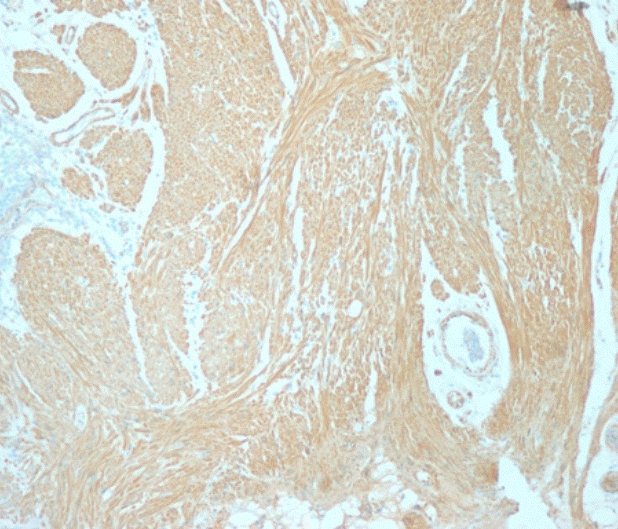

A 72-year-old woman came to the outpatient department for upper endoscopy, colonoscopy, and abdominal sonography due to indigestion. She was taking calcium channel blocker for hypertension with gastrointestinal motility drugs due to chronic indigestion. At age 67, she was diagnosed with breast cancer and underwent right mastectomy. At the endoscopy center, vital signs were stable. Blood tests showed no abnormal results. Abdominal sonography showed a hepatic cyst, a renal cyst, and bilateral renal parenchymal disease was suspected. Reflux esophagitis with chronic superficial gastritis was observed on upper endoscopy examination. Colonoscopy examination revealed several diverticula at the hepatic flexure and the sigmoid colon. A sessile nodular type polyp measuring about 0.8 cm with pale mucosa demarcated from the surrounding normal mucosa was noted on the distal rectum (Fig. 1). Injection with a mixture of carmine and saline was done to lift the lesion for polypectomy. The resected surface showed no remnant tissue from the polypoid lesion. To prevent bleeding after polypectomy, two endoclips (EZ Long, Olympus, Tokyo, Japan) were applied. The lesion was removed completely. Immunohistological findings were negative for cluster of differentiation (CD) 34 and CD117 but positive for caldesmon (Fig. 2). Leiomyoma arising from the muscularis mucosa was confirmed by pathology. No bleeding or perforation was noted after polypectomy.- Case 2